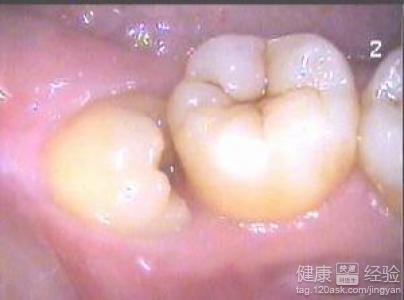

智齒什麼情況下要拔?

1對於我們正常人而言,人的智齒是可有可無的,有的人甚至到了五六十歲也沒有長智齒,這是非常常見的一種現象,但是大多數人在二十左右歲的時候都會長智齒,在長智齒的過程中如果不疼的情況下是沒問題。

2很多人長智齒的時候會出現牙疼的現象,也有的人會出現腰部疼痛,甚至會誘發牙周炎等疾病的產生,這種情況下一定要等這事稍微長出來了之後要將智齒拔掉,避免由於智齒出現其他牙齒的感染。

3這事如果疼的情況下一定要拔除,這樣可以有效的預防疾病,對人牙齒方面健康也是比較好的,但是智齒長的過程中並沒有任何的異樣的感覺,有的人甚至都不知道自己長了智齒,這種情況下可以不拔除。